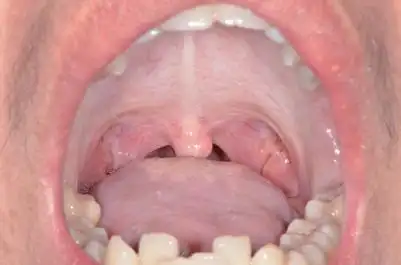

【求助】口腔黏膜病变 [病例帖]

看一下患者颊粘膜 - 口腔医学专业讨论版 - 爱爱医医学论坛